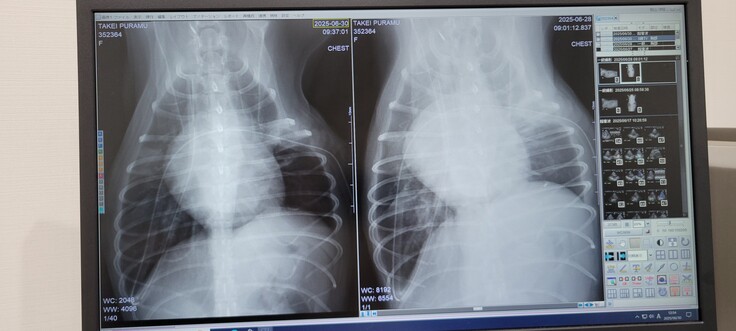

↓の通り術後に溜まっていた水も抜け、写真の体の右側の肺も少し膨らみが戻りつつあり、順調のようです。

(右が術後の26日(木)で、左が今日30日(月))

あとは現在の40%という高濃度の酸素室からうまく離脱できるかどうかと、点滴が外れた代わりに、ちゃんと薬を飲んでくれるかどうかですね。(手術は無事終わりましたが、若干の逆流は残っているので、これからも薬とは付き合っていく必要があります。)